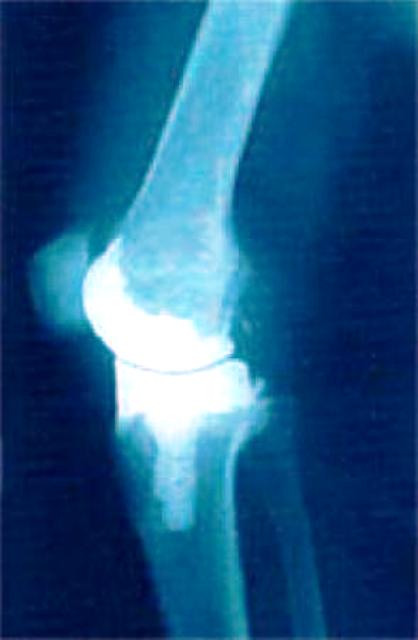

“Lo spacer è l’elemento in cemento osseo che viene messo al posto della protesi al momento dell’intervento di rimozione, consentendo al paziente di continuare a muovere e usare, almeno parzialmente, l’arto interessato in attesa del nuovo impianto – spiega Roberto Giardino, direttore del Laboratorio di Studi Pre-clinici Chirurgici del Rizzoli che ha condotto la sperimentazione insieme alla Microbiologia dell’Azienda Ospedaliero-Universitaria di Bologna S.Orsola-Malpighi, alla Farmacologia dell’Università di Verona e a Tecres, l’azienda veronese che dieci anni fa ha brevettato lo spacer esportandolo poi in tutto il mondo.

L’invenzione dello spacer aveva aperto la strada all’idea di una terapia locale, visto il posizionamento del dispositivo che gli consente di rilasciare direttamente nella sede dell’infezione i farmaci con cui viene “caricato”. Finora però lo spacer conteneva un solo antibiotico e gli effetti sull’infezione erano insoddisfacenti: la terapia doveva comunque essere completata da un lungo trattamento di tipo sistemico, con tutte le note controindicazioni.